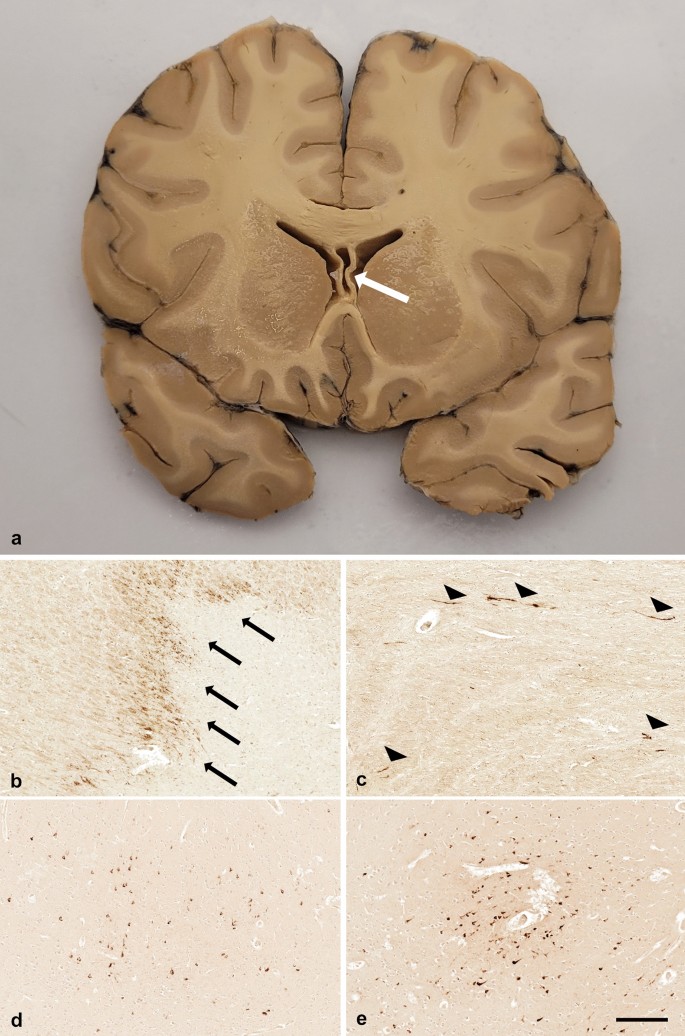

a Examination of the brain revealed evidence of diffuse brain swelling, with ventricular effacement but no measurable midline shift. Cavum septum pellucidum was present (white arrow). On microscopy, waves of punctate to granular APP-immunoreactive axons were present consistent with the vascular complications of raised intracranial pressure (b, arrows), in addition to scattered linear and fusiform axonal profiles with the stereotypical appearance and distribution of DAI (c, arrowheads). Multiple patchy foci of p-tau-immunoreactive neuronal profiles were present within the neocortex, typically at sulcal depths (d) with, in several locations, perivascular clustering of p-tau-immunoreactive neurons consistent with the pathognomonic lesion of CTE-NC (e). Scale bar 250 µm b–e

Sections stained for APP revealed immunoreactive axons in two distinct patterns. In and around the deep gray nuclei and surrounding the hemorrhagic focus in the pons, waves of APP-immunoreactive axons typical of the vascular complications of raised intracranial pressure were present (Fig. 1b) [[10](/article/10.1007/s00401-023-02576-y#ref-CR10 "Reichard RR, Smith C, Graham DI (2005) The significance of β-APP immunoreactivity in forensic practice. Neuropathol Appl Neurobiol 31:304–313. https://doi.org/10.1111/j.1365-2990.2005.00645.x